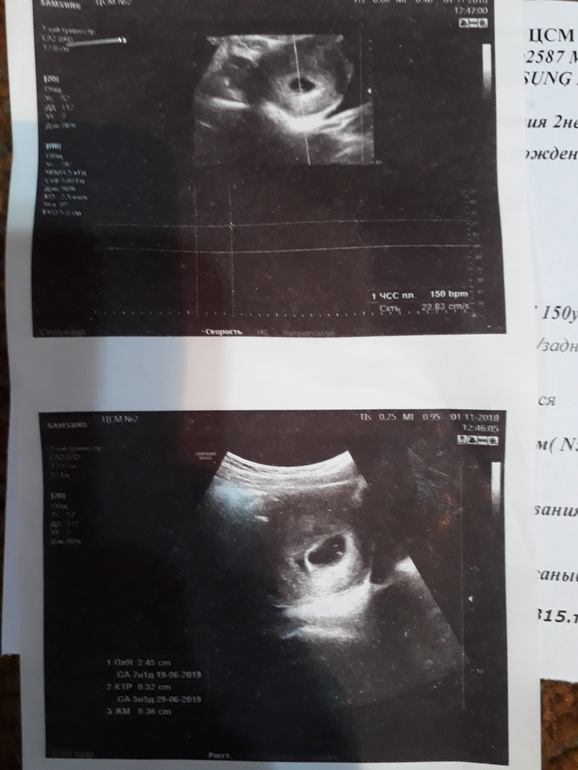

adiletsalkyn → Новенькая Спам Мама мальчика (8 лет) Бишкек Помогите разобраться двое или один ? Но врачи не чего не сказали.а может там однояцевые близнецы? Читать далее